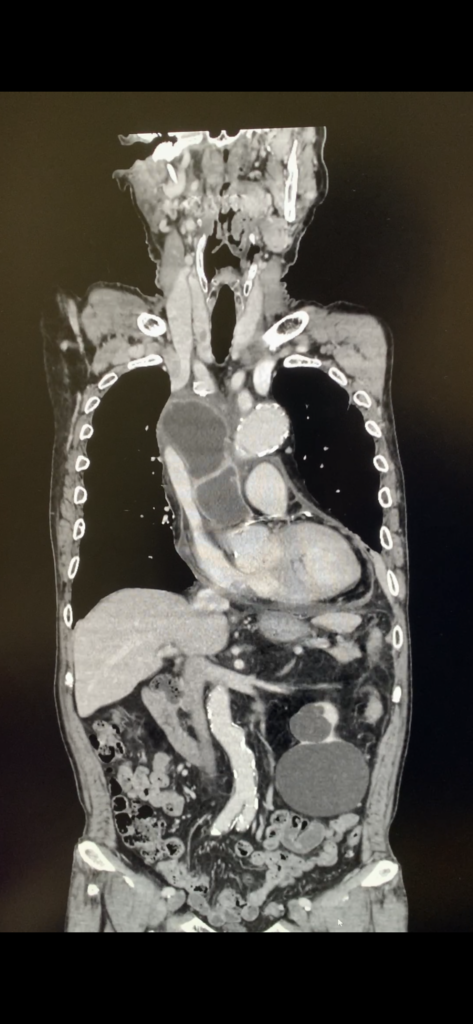

医療 おしりの出血や飛び出しや痛み=肛門の診察 2025年6月20日 2025年6月20日 Toshi Facebook Twitter Google+ はてブ Pocket Feedly おしりの出血や飛び出しや痛み ヘモ?膿瘍?マリグナンシー? たんなる裂肛というのもあるよね そのあたりのフレームワークで考えればいいんじゃないかと。 大きさとかはピンキリ。 やっぱりあの肛門鏡暗いよ! Facebook Twitter Google+ はてブ Pocket Feedly